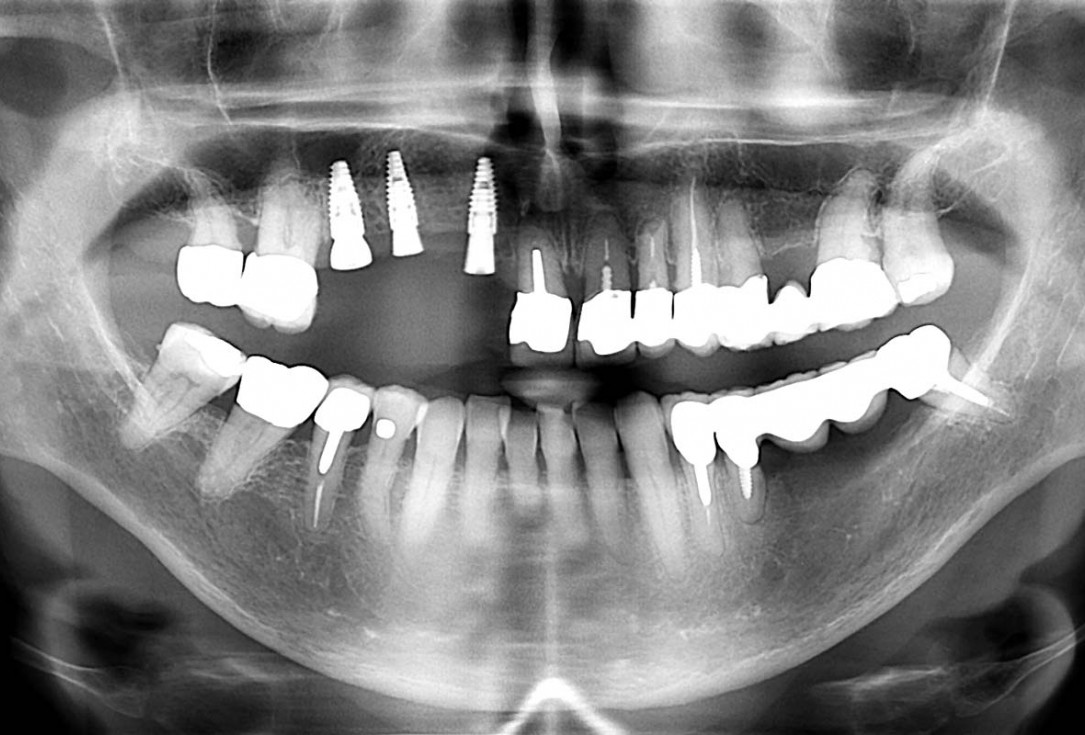

Initial x-ray, ten years post implantationem alio loco, large peri-implant bone loss